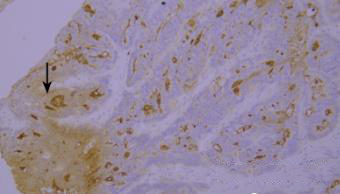

染色液的堆积(黑色箭头区域)。

优化建议:

充分洗涤。

7.干片

干片导致的假阴性(黑色箭头区域)。

加入Tween-20的缓冲液能够更好地防止切片干燥。

8.边缘效应

边缘效应造成的非特异性染色(黑色箭头区域)。

组织切片与玻片黏贴牢固,试剂完全覆盖组织防止干片,加入Tween-20的缓冲液能够更好地防止边缘效应。